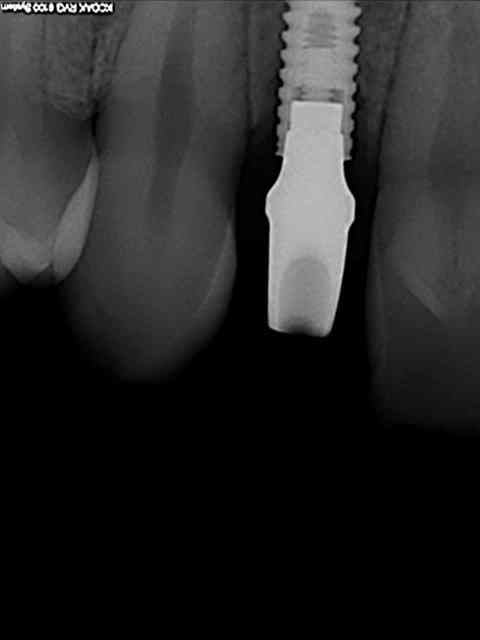

tes implants 12 et 13 n'ont pas le même niveau d'enfouissement, tu n'as pas peur d'une lyse osseuse de 13 pour venir au niveau du col de 12 ?

01/09/2010 à 16h54

-1 ou 2 mois plus tard ( je sais plus)

- empreinte avec transfert pop in

- pilier zircone esthétique Axiom

- prothèse et pilier

- pilier zircone en place

- couronne en place (petite compression gingivale)

fin du traitement